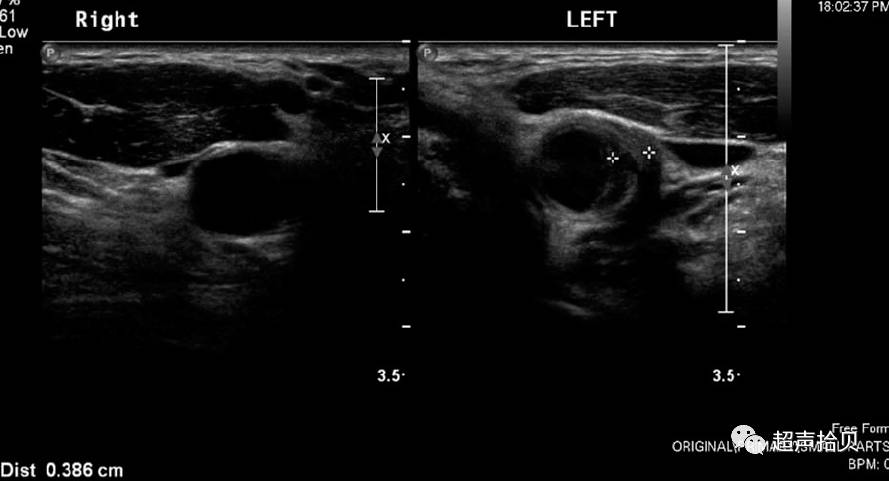

图2.男,左侧颈总动脉的横断面声像图,颈总动脉外侧壁的颈动脉病变,对侧对比正常。